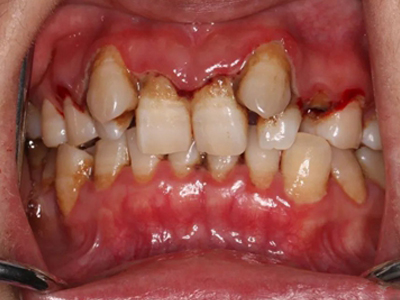

急性坏死性溃疡性龈炎起病急,病程短,常为数天至1-2周,以龈乳头和龈缘的坏死为其特征性损害,尤以下前牙多见,初起时龈乳头充血水肿,个别龈乳头顶端可发生坏死性溃疡,上覆有灰白色坏死物,中央凹下如火山口状。龈缘如虫蚀状,坏死区出现灰褐色假膜,擦去后可见出血创面。龈乳头被破坏后与龈缘成一直线,如刀切状。病损一般不波及附着龈,患处牙龈极易出血,疼痛明显并有腐败性口臭。

重症患者可有低热、疲乏等全身症状,并可伴有下颌下淋巴结肿大和压痛。有的患者可能进展为坏死性龈口炎、坏死性溃疡性牙周炎等疾病,从而导致牙周袋形成、牙槽骨吸收和牙齿松动。

急性坏死性溃疡性龈炎是一种由多种微生物(如梭形杆菌、螺旋体等)引起的机会性感染,当宿主局部抵抗力降低时,这些微生物的毒性物质可形成组织病损。已存在的慢性龈炎或牙周炎是本病发生的重要条件。吸烟史、精神紧张、过度疲劳、营养不良、全身消耗性疾病等,易诱发本病。